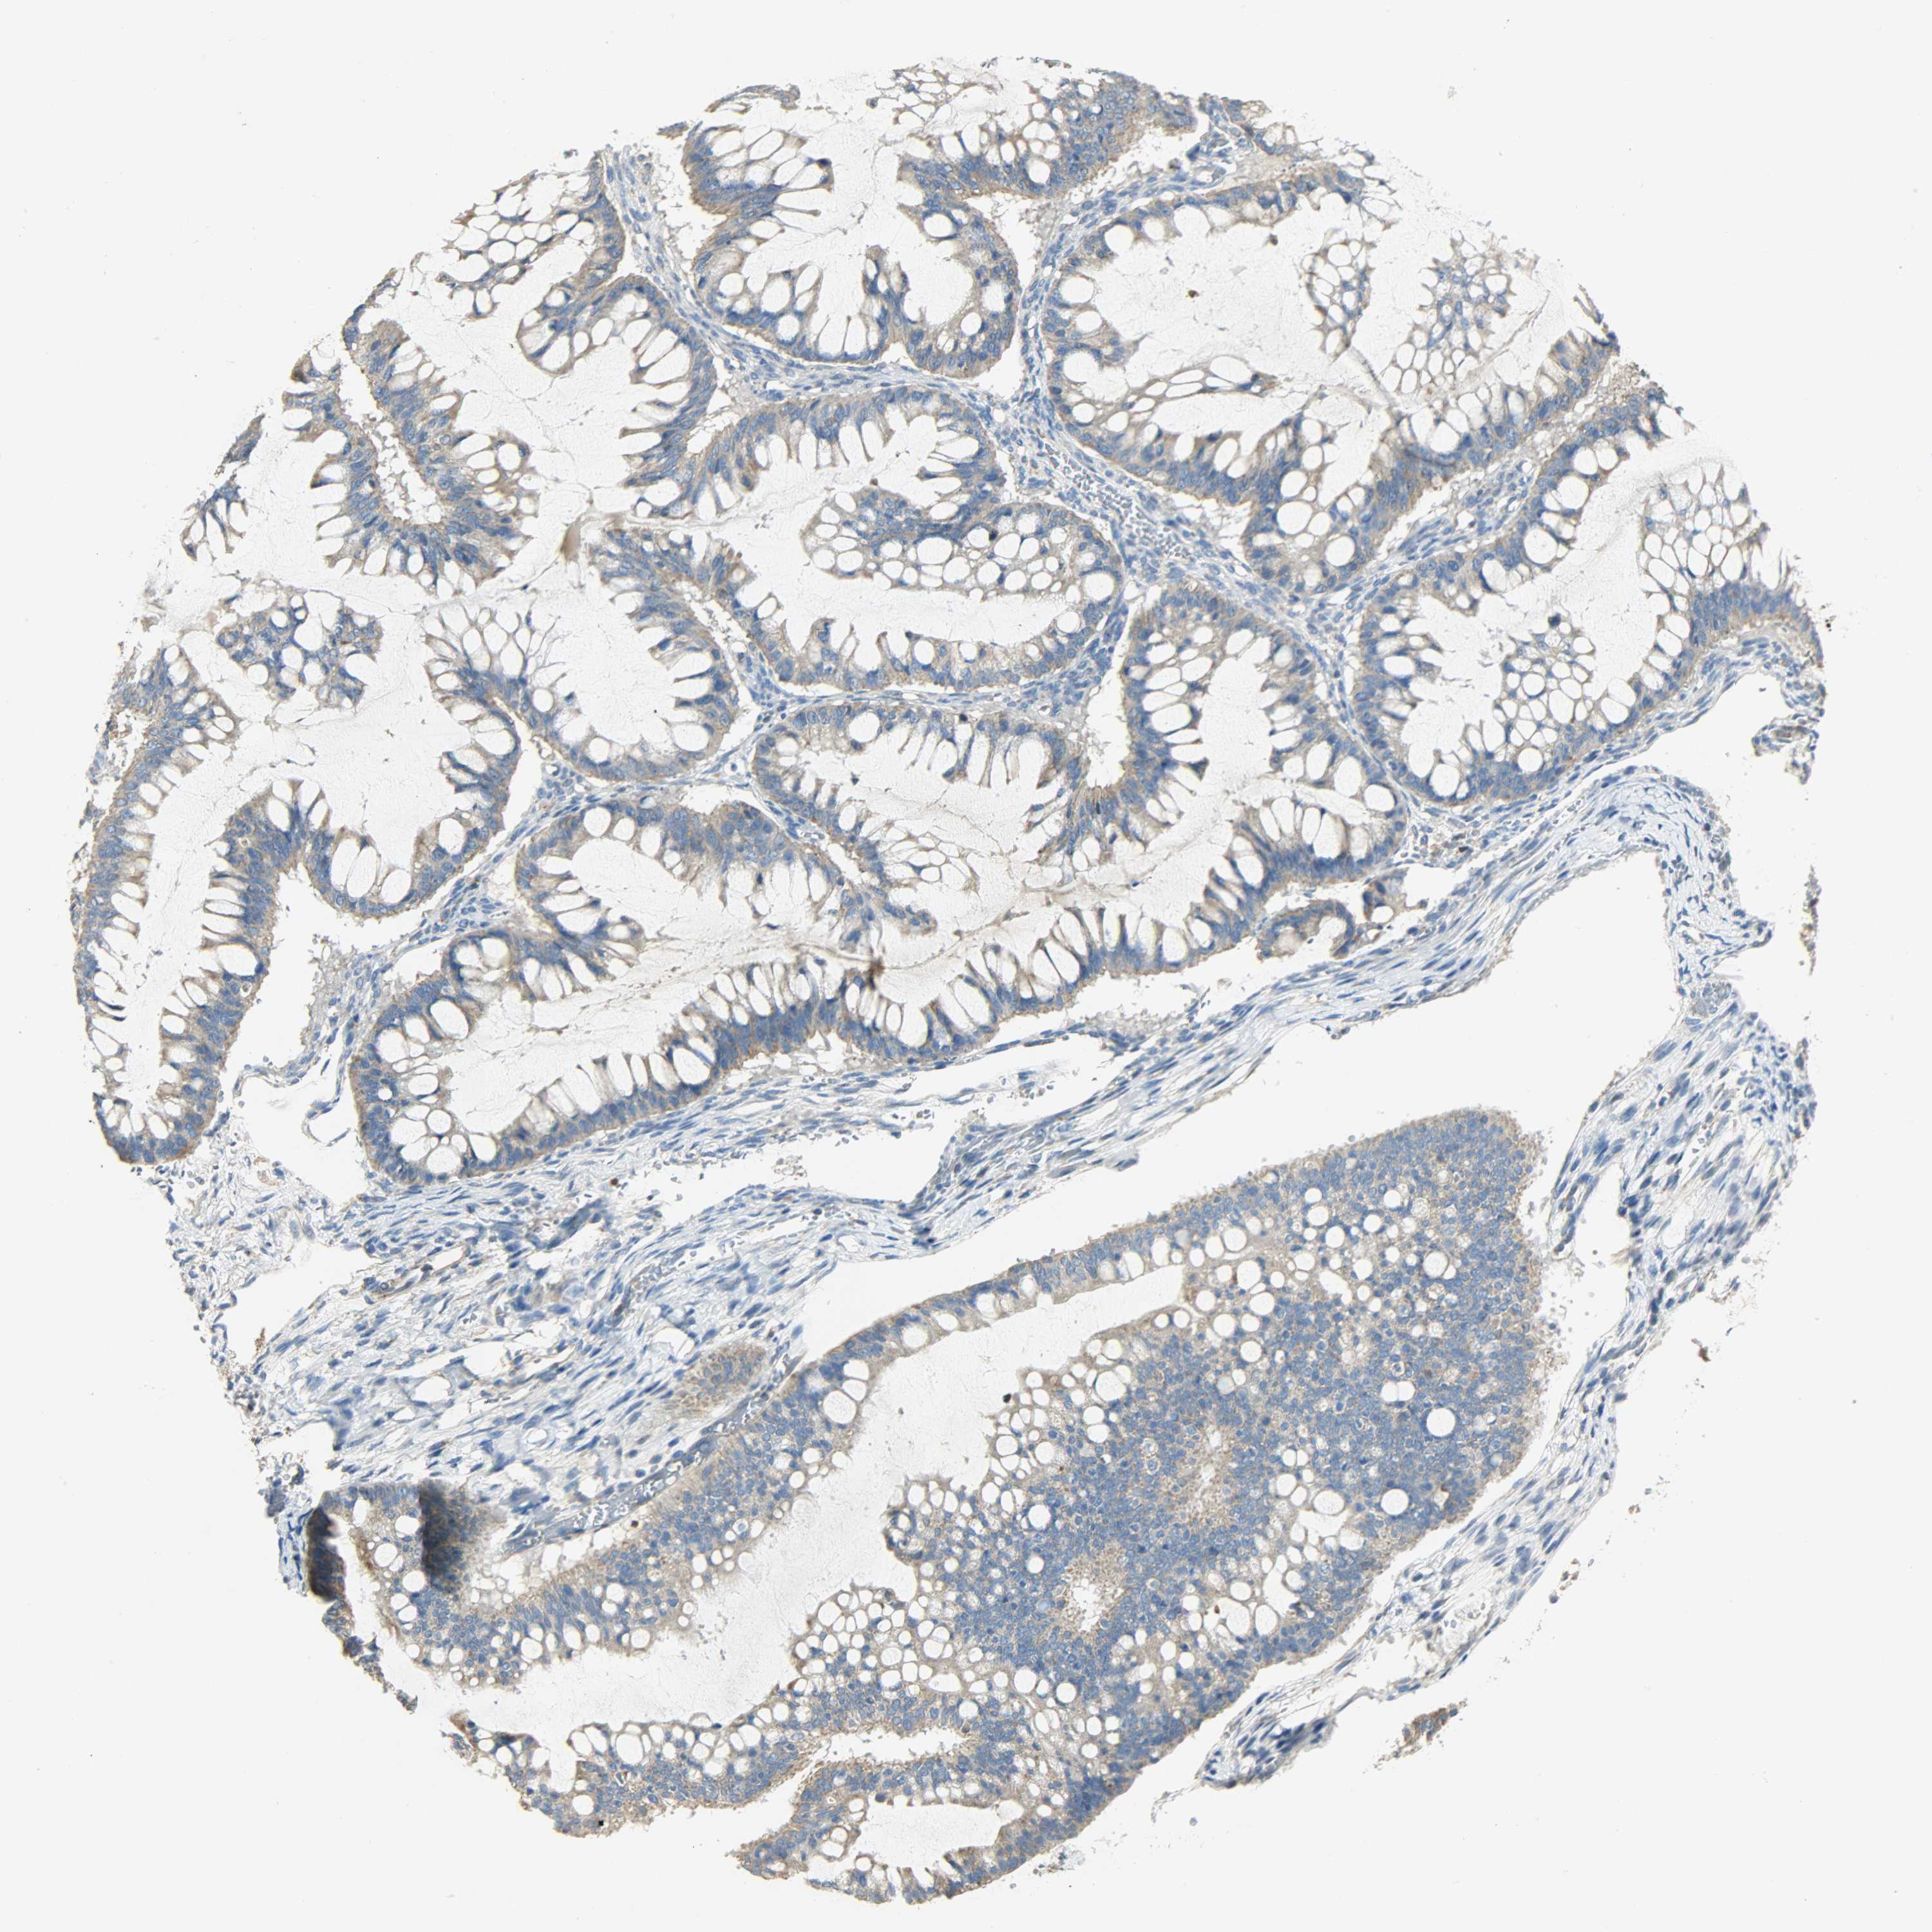

OVARIAN CANCER - Protein expressioni

A mouse-over function shows sample information and annotation data. Click on an image to view it in a full screen mode. Samples can be filtered based on level of antibody staining by selecting one or several of the following categories: high, medium, low and not detected. The assay and annotation is described here.

Note that samples used for immunohistochemistry by the Human Protein Atlas do not correspond to samples in the TCGA dataset.

Antibody stainingi

Antibody staining in the annotated cell types in the current human tissue is reported as not detected, low, medium, or high, based on conventional immunohistochemistry profiling in selected tissues. This score is based on the combination of the staining intensity and fraction of stained cells.

Each image is clickable and will lead to virtual microscopy that enables deeper exploration of all samples and also displays staining intensity scores, fraction scores and subcellular localization as well as patient and tissue information for each sample.

Antibody HPA004829

Antibody CAB004975

Staining

High

Medium

Low

Not detected

Intensity

Strong

Moderate

Weak

Negative

Quantity

>75%

75%-25%

<25%

None

Location

Nuclear

Cytoplasmic/membranous

Cytoplasmic/membranous,nuclear

Cystadenocarcinoma, serous, NOS

Carcinoma, endometroid

Carcinoma, NOS

Cystadenocarcinoma, mucinous, NOS